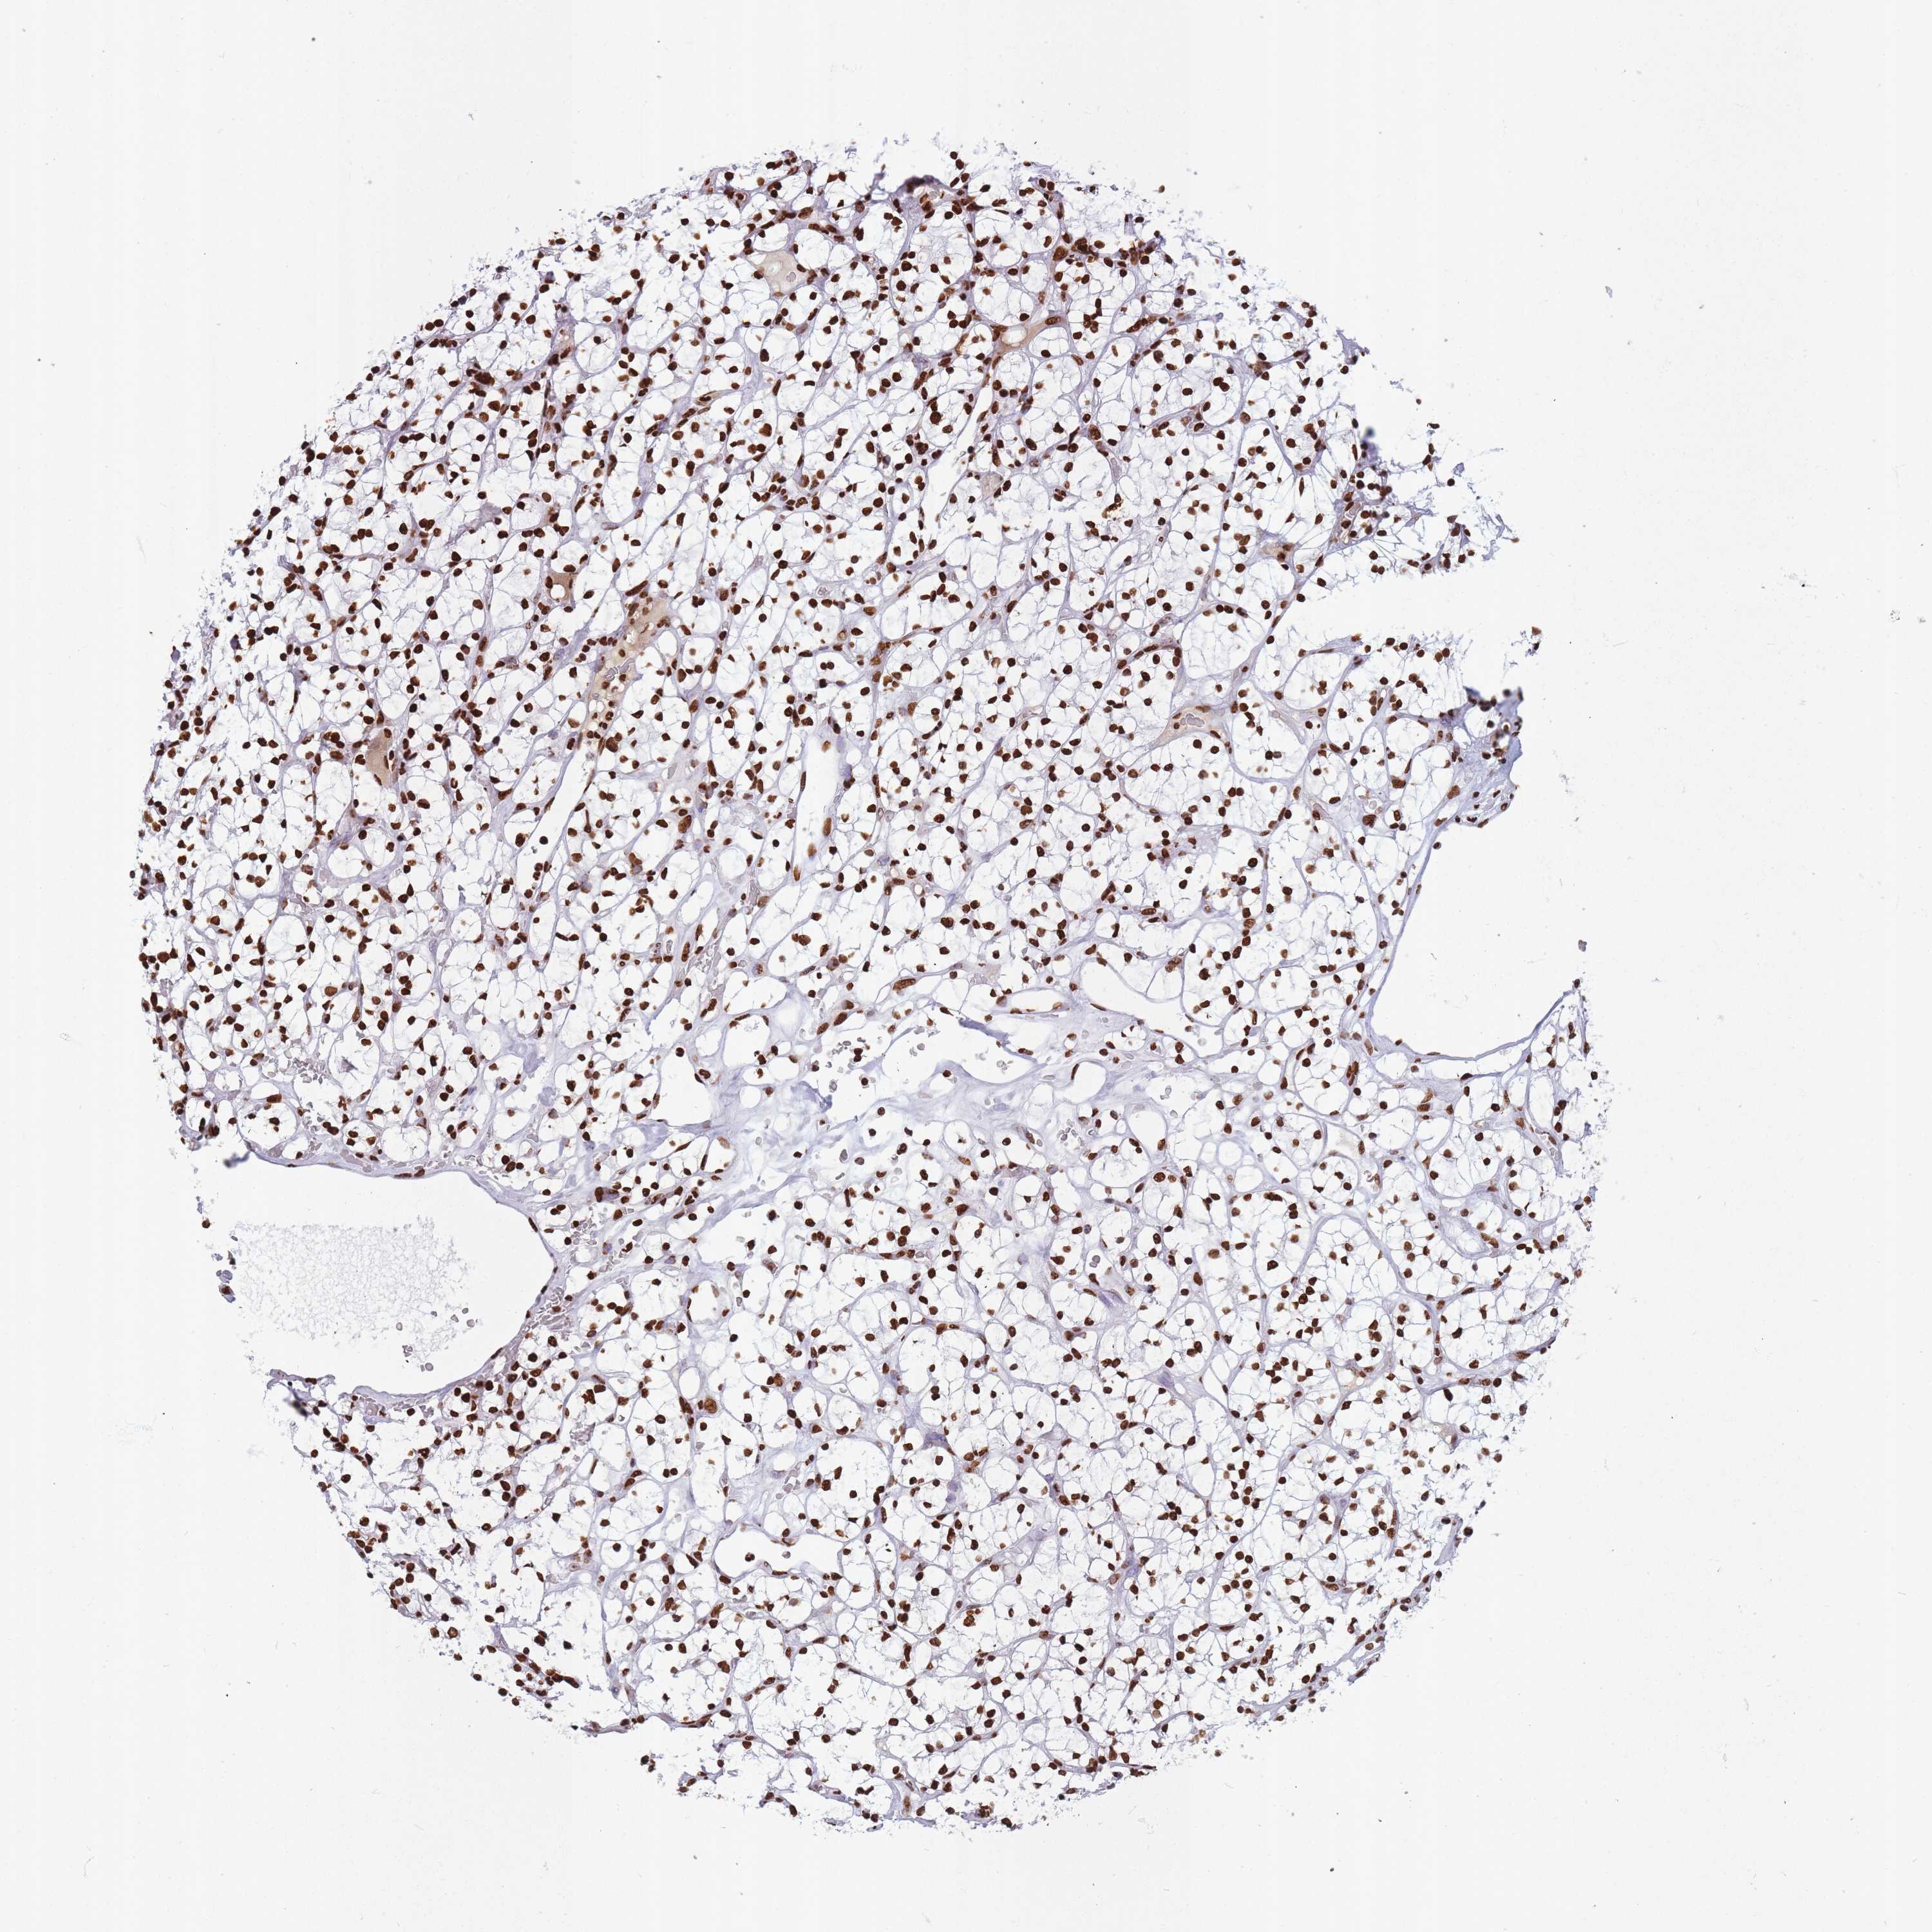

KIDNEY RENAL CLEAR CELL CARCINOMA (VALIDATION) - Interactive survival scatter ploti

The Survival Scatter plot shows the clinical status (i.e. dead or alive) for all individuals in the patient cohort, based on the same data that underlies the corresponding Kaplan-Meier plots. Patients that are alive at last time for follow-up are shown in blue and patients who have died during the study are shown in red.

The x-axis shows the expression levels (FPKM) of the investigated gene in the tumor tissue at the time of diagnosis. The y-axis shows the follow-up time after diagnosis (years). Both axes are complimented with kernel density curves demonstrating the data density over the axes. The top density plot shows the expression levels (FPKM) distribution among dead (red) and alive patients (blue). The right density plot shows the data density of the survived years of dead patients with high and low expression levels respectively, stratified using the cutoff indicated by the vertical dashed line through the Survival Scatter plot. This cutoff is automatically defined based on the FPKM cutoff that minimizes the p-score. The cutoff can be changed by dragging the vertical line or by entering a cutoff value in the square labeled "Current cut-off".

Under the Survival Scatter plot the p-score landscape (black curve; left axis) is shown together with dead median separation (red curve; right axis). Dead median separation is the difference in median mRNA expression between patients who have died with high and low expression, respectively. It is calculated as follows: median FPKM expression of dead patients with high expression - median FPKM expression of dead patients with low expression. This is intended to aid the user in visually exploring custom cutoffs and the associated p-scores and dead median separation.

Individual patient data is displayed and can be filtered by clicking on one or more of the category buttons on the top of the page. Categories describing expression level and patient information include: high, low, alive, dead, female, male and tumor stages. The scale of the x-axis can be toggled between linear and log-scale by clicking on the "x log" button. Mouse-over function shows TCGA ID, patient information and mRNA expression (FPKM) for each patient.

& Survival analysisi

Kaplan-Meier plots summarize results from analysis of correlation between mRNA expression level and patient survival. Patients were divided based on level of expression into one of the two groups "low" (under cut off) or "high" (over cut off). X-axis shows time for survival (years) and y-axis shows the probability of survival, where 1.0 corresponds to 100 percent.

HNRNPUL1 is not prognostic in Kidney Renal Clear Cell Carcinoma (validation)

Best expression cut offi

Based on the FPKM value of each gene, patients were classified into two groups and association between prognosis (survival) and gene expression (FPKM) was examined. The best expression cut-off refers the FPKM value that yields maximal difference with regard to survival between the two groups at the lowest log-rank P-value. Best expression cut-off was selected based on survival analysis .

When clicking on this number, the vertical dashed line indicating cut-off, the interactive survival plot, and the Kaplan-Meier curve will be adjusted to show results based on the best expression cut-off.

: 98.91

Median expressioni

Median expression refers to the median FPKM value calculated based on the gene expression (FPKM) data from all patients in this dataset. When clicking on this number, the vertical dashed line indicating cut-off, the interactive survival plot, and the Kaplan-Meier curve will be adjusted to show results based on the median expression.

: N/A

Median follow up timei

Median follow up time refers to the median time (years) after diagnosis with this type of cancer, based on clinical data from all patients in this dataset.

P scorei

Log-rank P value for Kaplan-Meier plot showing results from analysis of correlation between mRNA expression level and patient survival.

N/A

5-year survival highi

5-year survival for patients with higher expression than the expression cutoff.

For melanoma and glioma, 3-year survival is shown.

5-year survival lowi

5-year survival for patients with lower expression than the expression cutoff.

TCGA RNA samplesi

RNA-seq data is reported as average FPKM (number Fragments Per Kilobase of exon per Million reads), generated by the The Cancer Genome Atlas (TCGA) .

Normal distribution across the dataset is visualized with box plots, shown as median and 25th and 75th percentiles. Points are displayed as outliers if they are above or below 1.5 times the interquartile range. FPKM values of the individual samples are presented next to the box plot.

Average pTPM 89.2

Number of samples 100